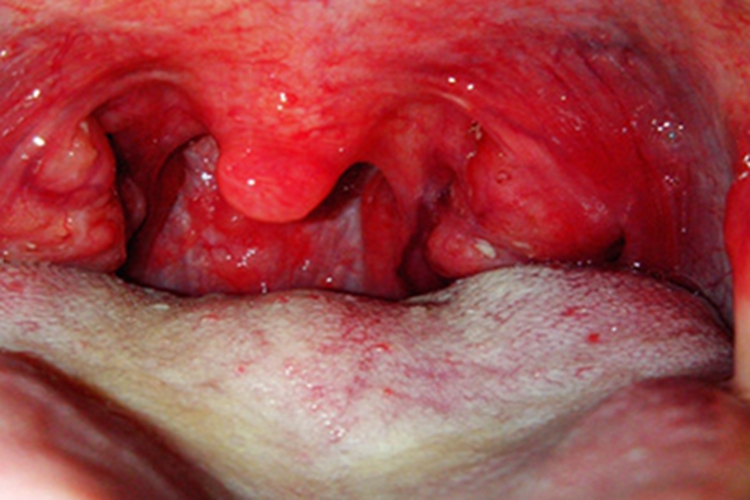

急性化脓性扁桃体炎包括急性滤泡性扁桃体炎和急性隐窝性扁桃体炎。本病起病急,可有畏寒、高热、头痛、食欲下降、乏力、全身不适、便秘等全身症状,还可出现扁桃体肿大、周围充血,咽喉部位红肿。其中急性滤泡性扁桃体炎可见圆形黄白色化脓性滤泡,急性隐窝性扁桃体炎在隐窝口处有黄色点状渗出物,并且可融合成假膜,还可出现下颌淋巴结肿大等症状。